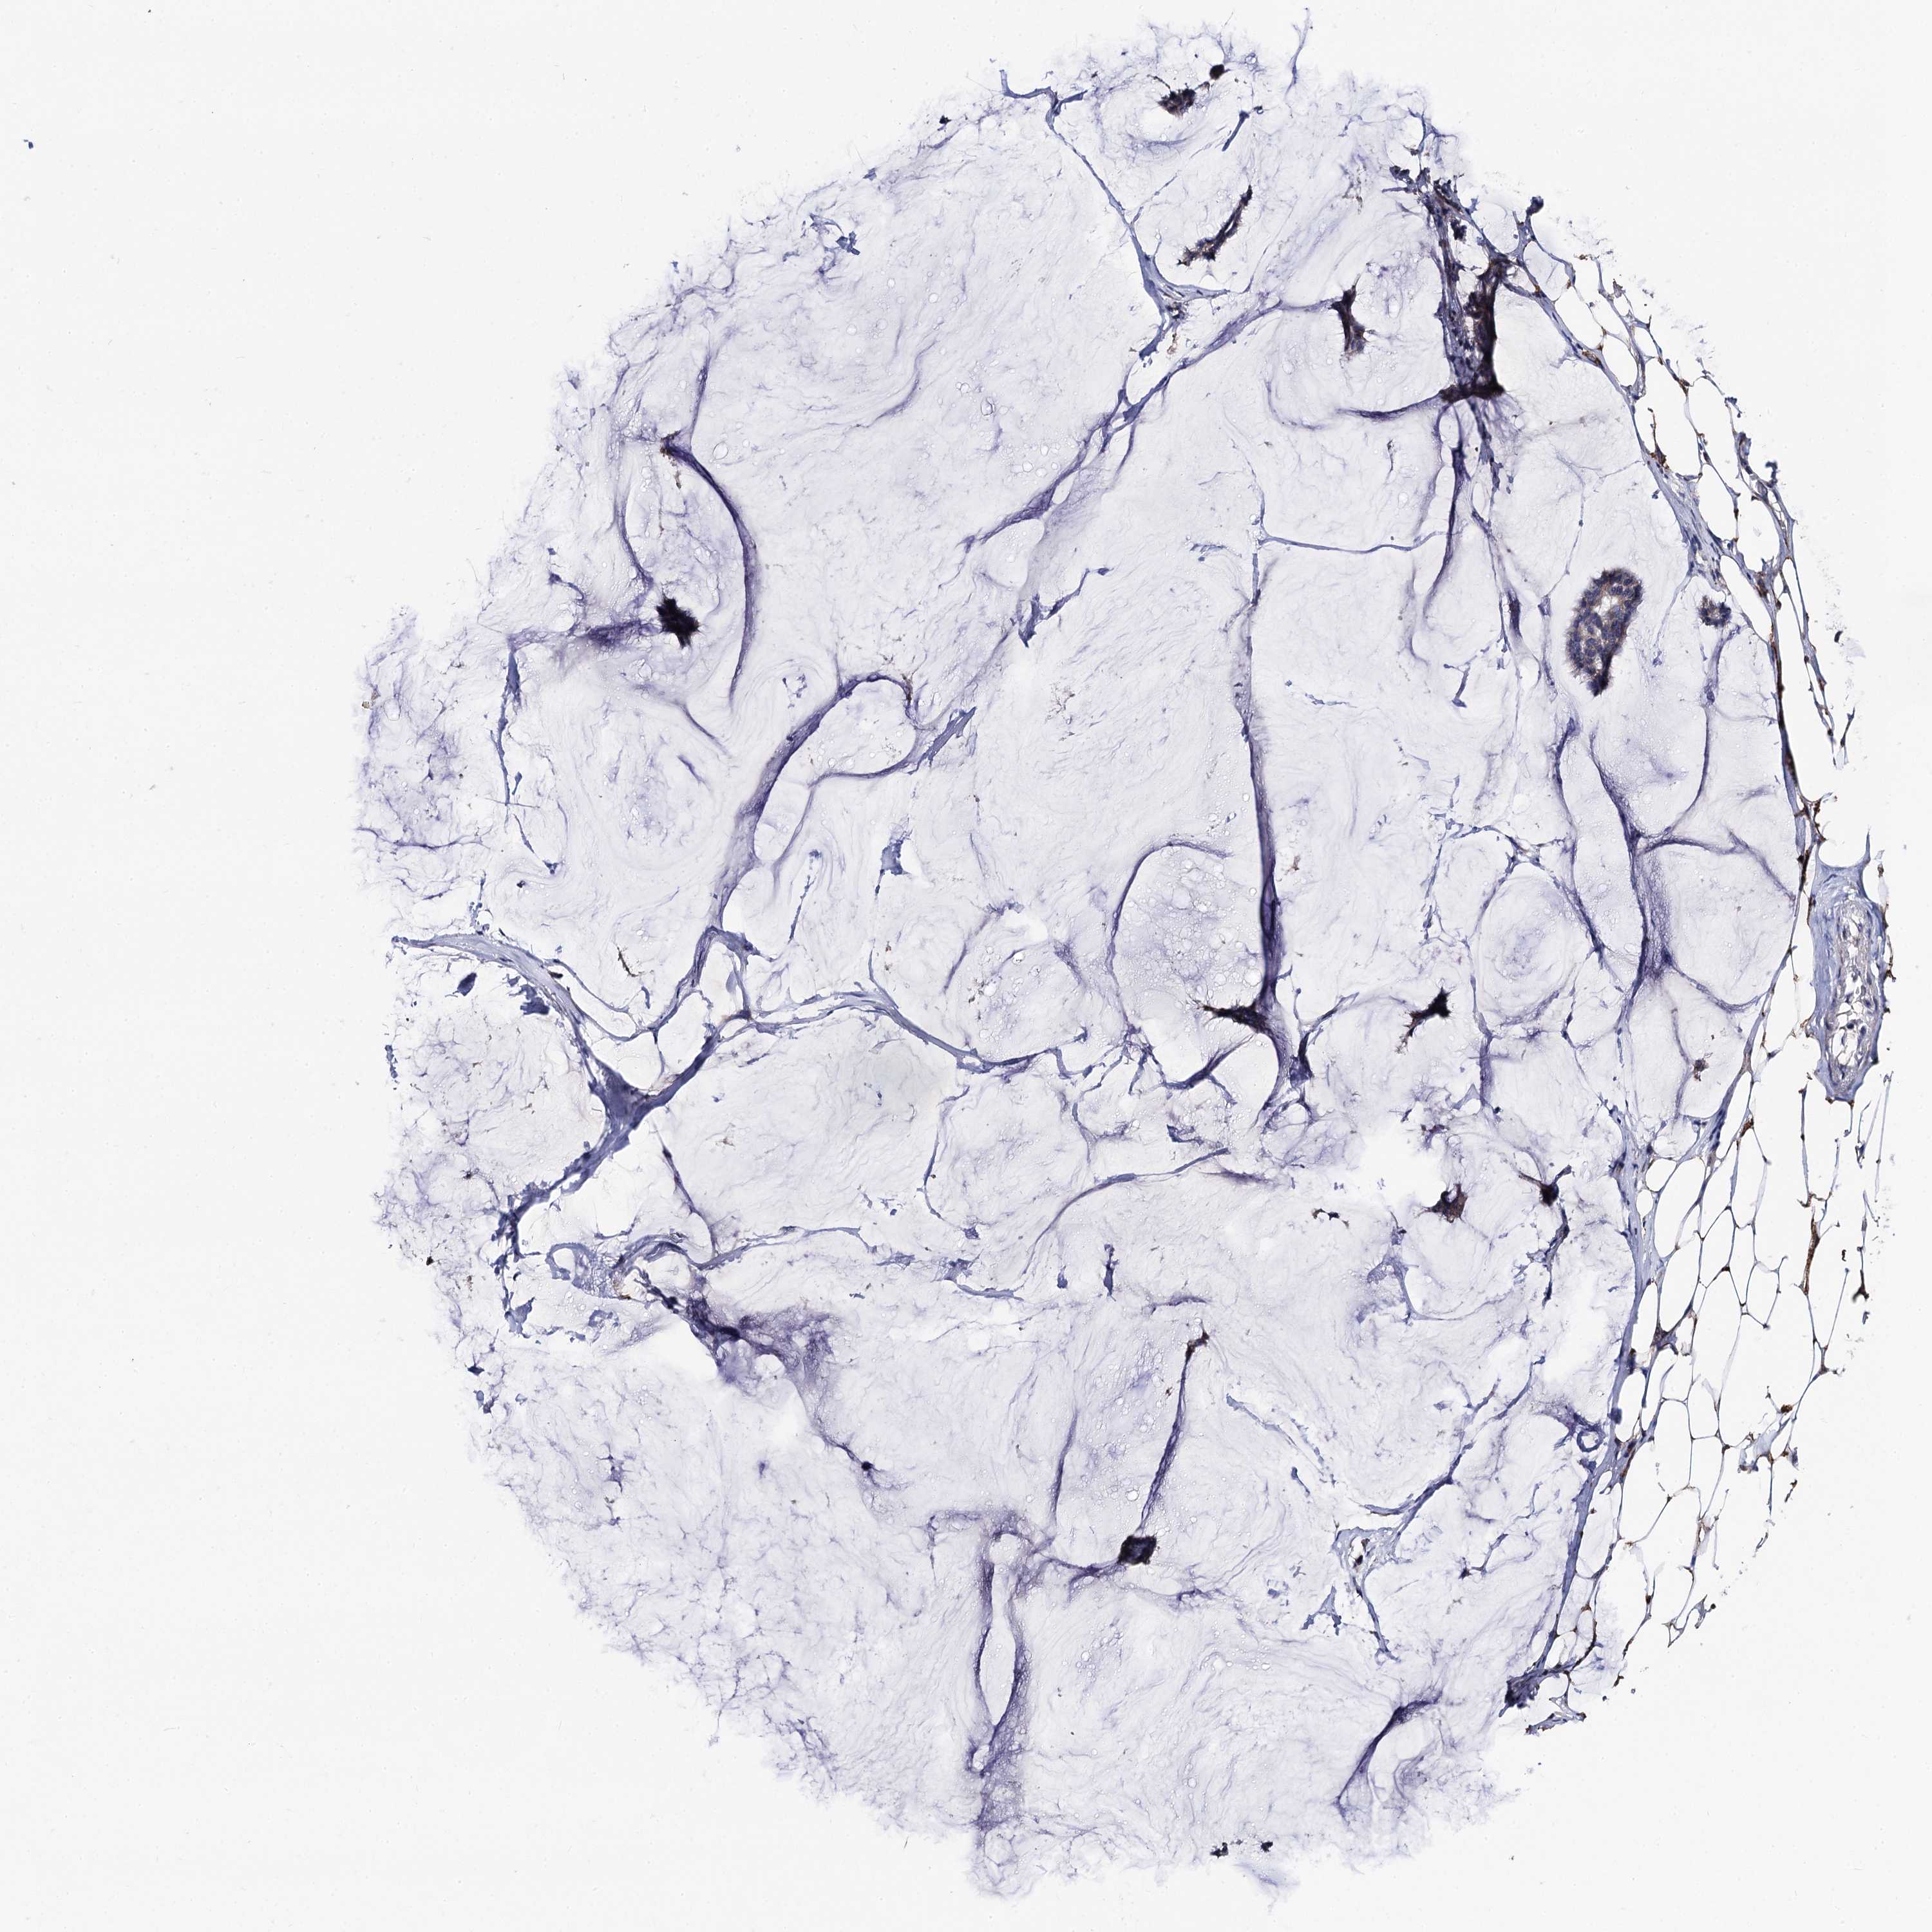

CANCER BREAST CANCER Show tissue menu

BRCA TCGA BRCA VALIDATION PROTEIN EXPRESSION